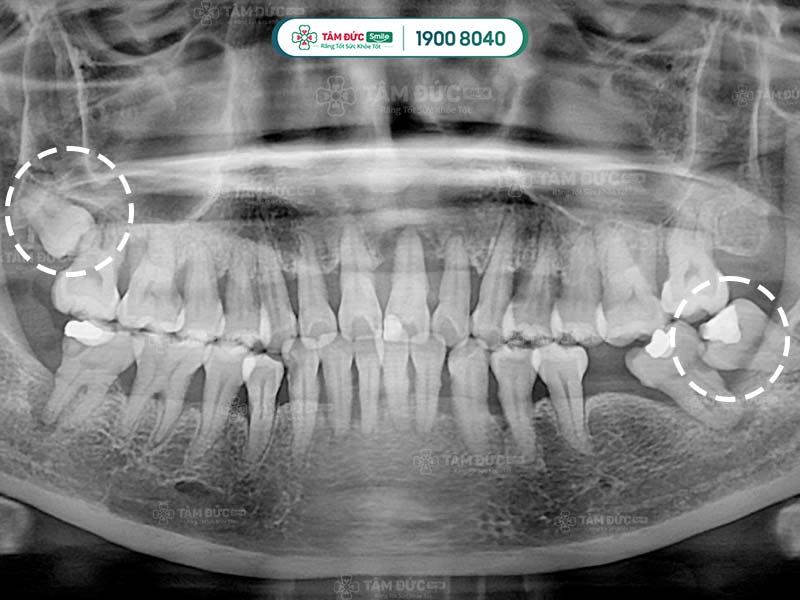

phim x-quang răng khôn mọc lệch

Răng khôn mọc lệch nên nhổ từ sớm